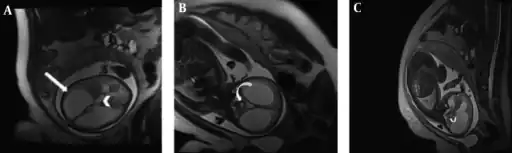

Aqueductal stenosis in a fetus a) Axial b) coronal c) sagittal